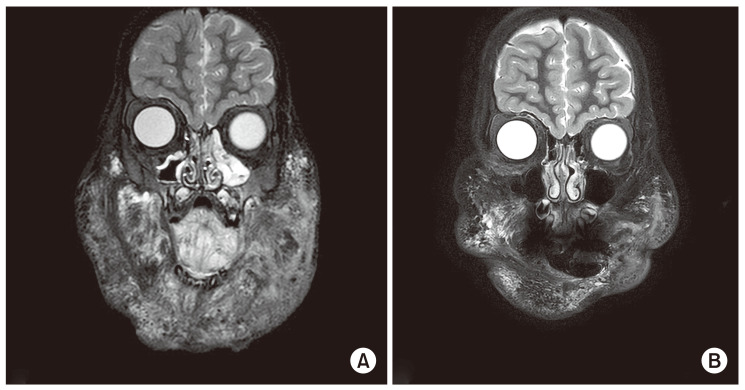

A significant to moderate reduction in mass volume in the radiologic evaluation was observed in 40 patients, ranging from 20.2% to 94.8%. Eight of the 15 patients who had a volume reduction of less than 20% on MRI showed clinical improvement such as external portion size reduction, relief of pain, and reduced bleeding episode (Fig. 2), and removal of tracheostomy and gastrostomy. As shown in Table 4, 51 patients (87.9%) showed results ranging from complete to partial, according to the evaluation of the disease response.

Even though it did not show a significant decrease in LM volume on imaging studies, the subjective satisfaction of patients or parents was quite considerable. Especially in case of complications with bleeding, the episode of bleeding and the amount of bleeding were dramatically decreased (Fig. 2). It might be associated with an antiangiogenic property of sirolimus.